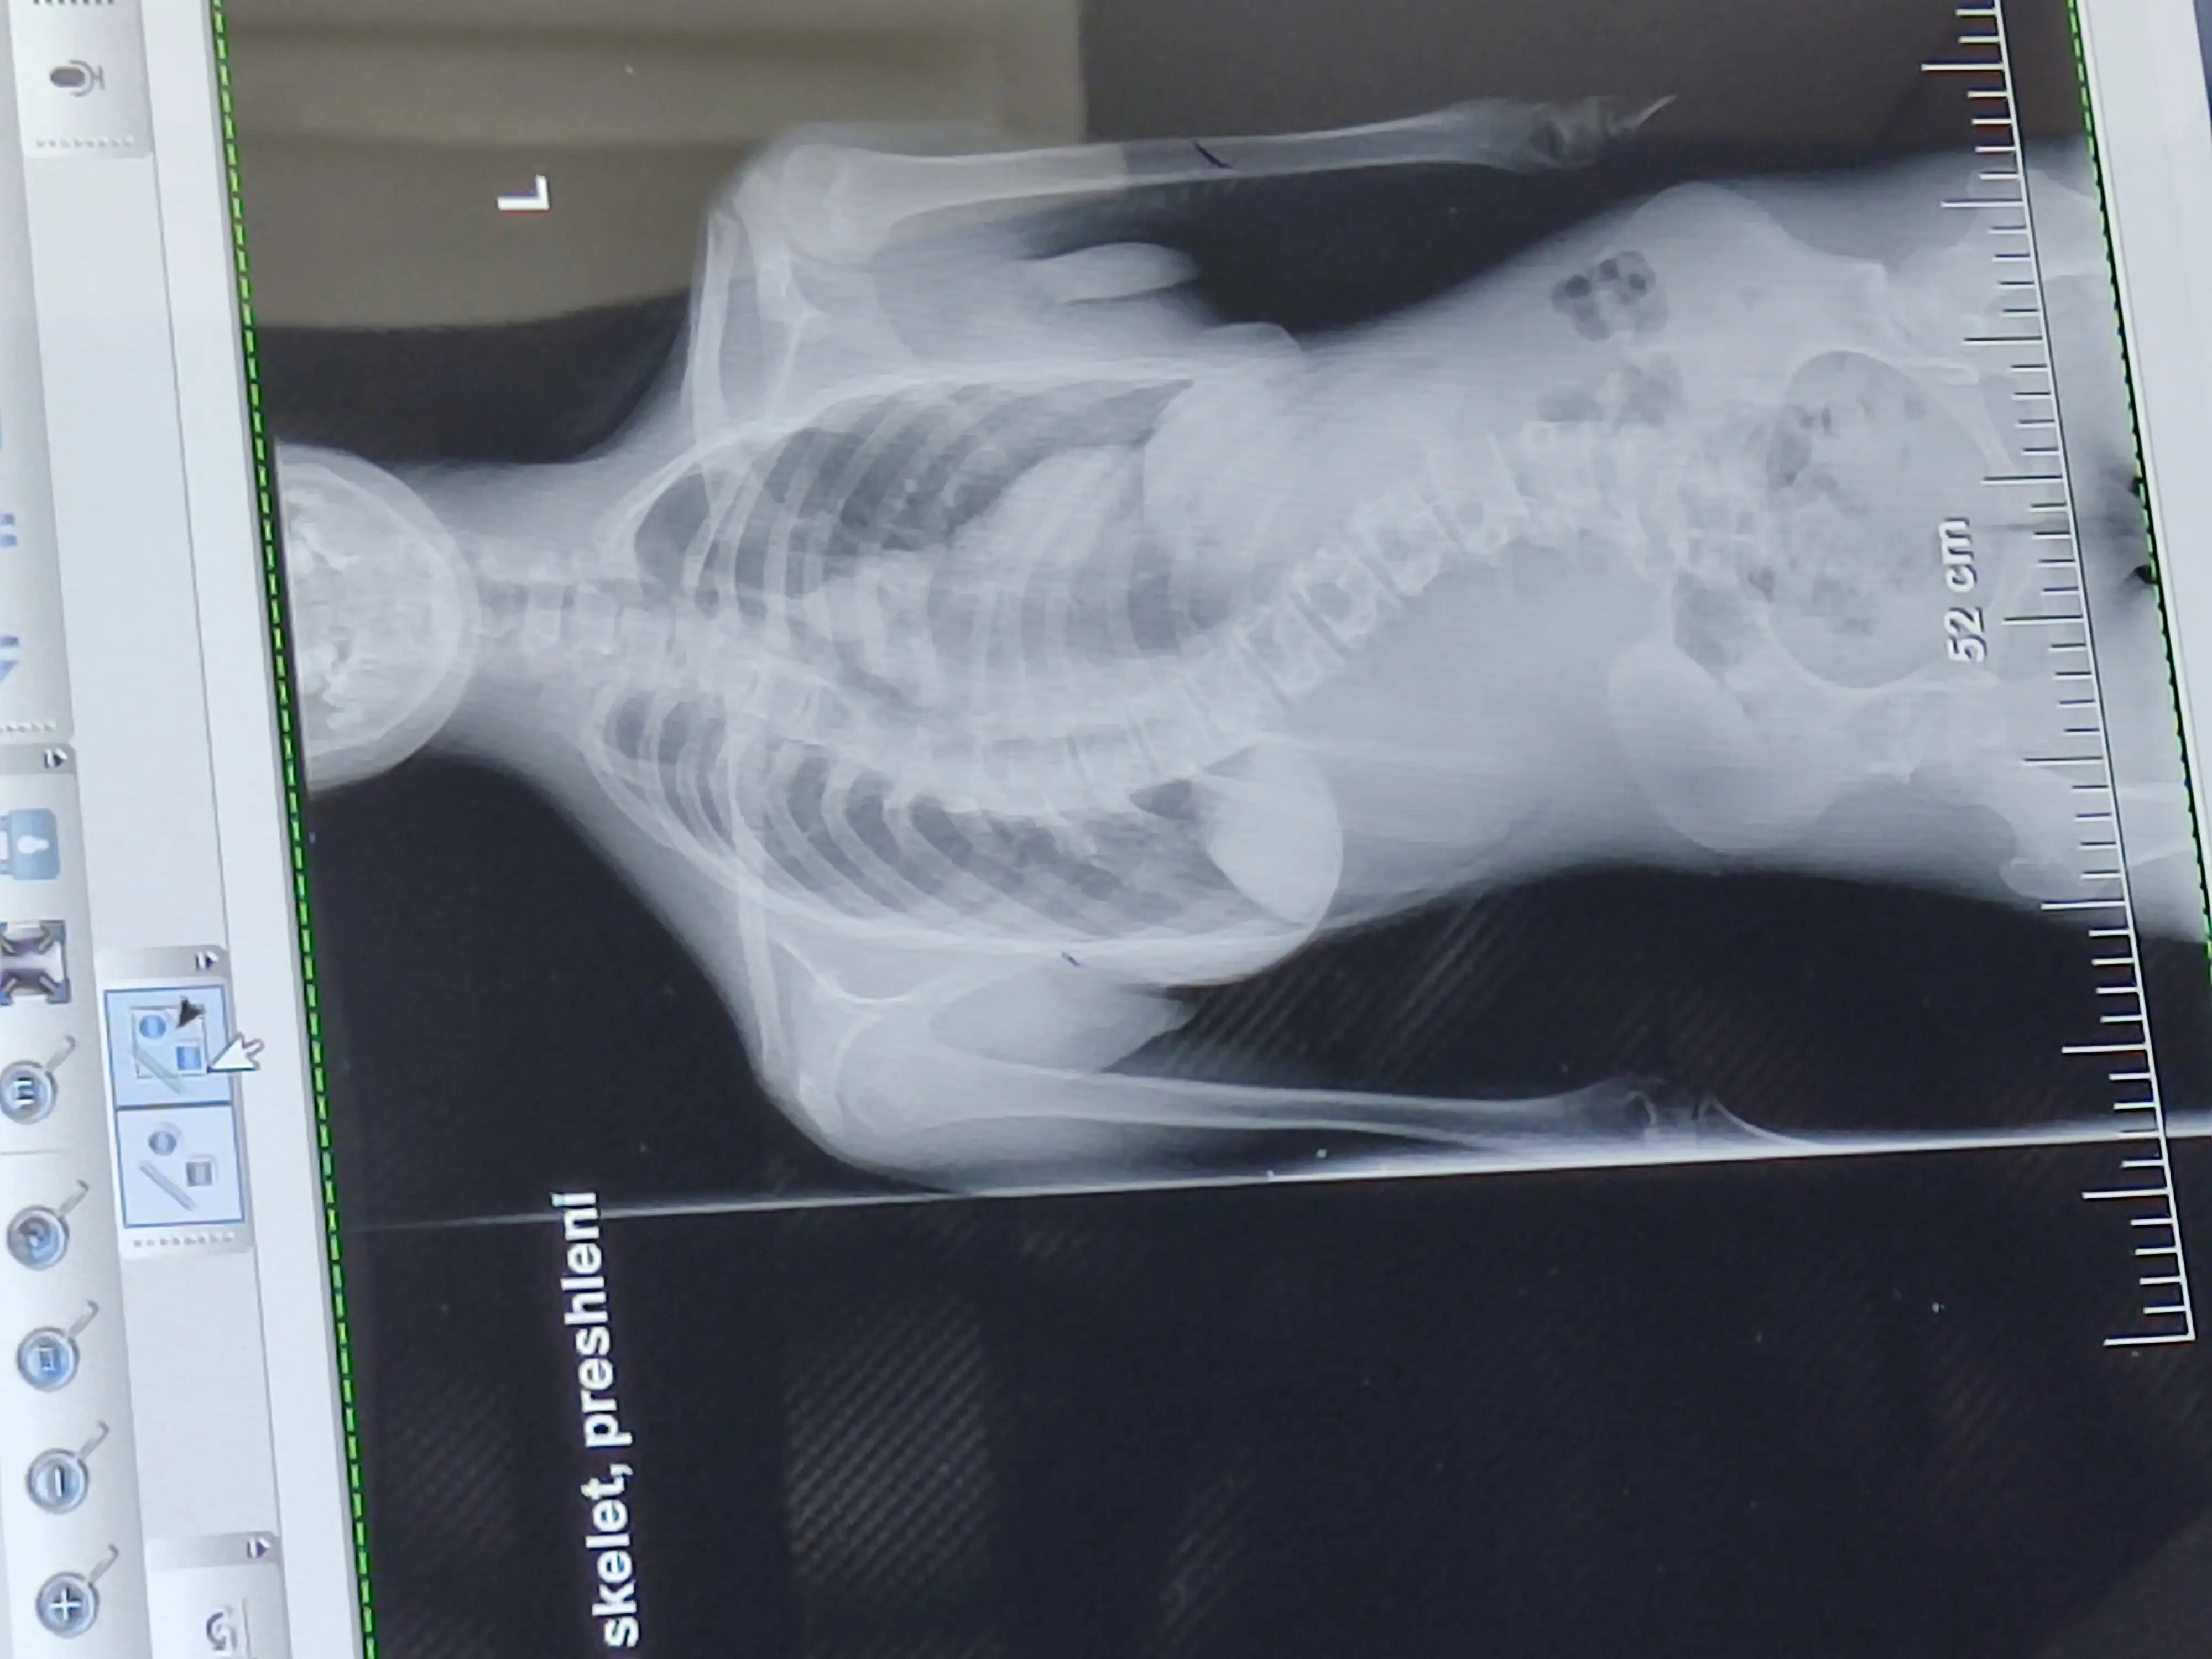

Здравейте хора с големи сърца! С болка Ви съобщавам, че с навлизането в пубертета при нашата прекрасна Айси аномалиите рязко прогресират и отново се нуждае от спешна операция на гръбнака в клиника в Истанбул. Дават ни 100% успешност на операцията, след поставянето на импланти по целия гръбначен стълб. За съжаление кривата прогресира с минути, поради аномалия и вече притиска сърцето и белия дроб и пречи на правилното им функциониране. Клиниката е готова да я приеме, за операция на 9 октомври, но до тогава трябва да бъде събрана непосилната за нас сума от 200 000 лв.  Моля Ви от сърце и душа, Помогнете на нашата Айси да живее и сбъдва мечтите си! Поклон пред всички Вас!

Hello people with big hearts! It pains me to inform you that as our lovely Aissi enters puberty, her abnormalities are progressing rapidly and she needs emergency spinal surgery again at a clinic in Istanbul. We are given a 100% success rate for the surgery, following the placement of implants throughout the spine. Unfortunately the curve progressed with minutes due to the abnormality and is now pressing on the heart and lung and preventing them from functioning properly. The clinic is ready to accept her, for surgery on October 9, but by then the prohibitive sum of 200,000 BGN must be raised. Please from the bottom of my heart and soul, Help our Aissy live and make her dreams come true! We bow to all of you!